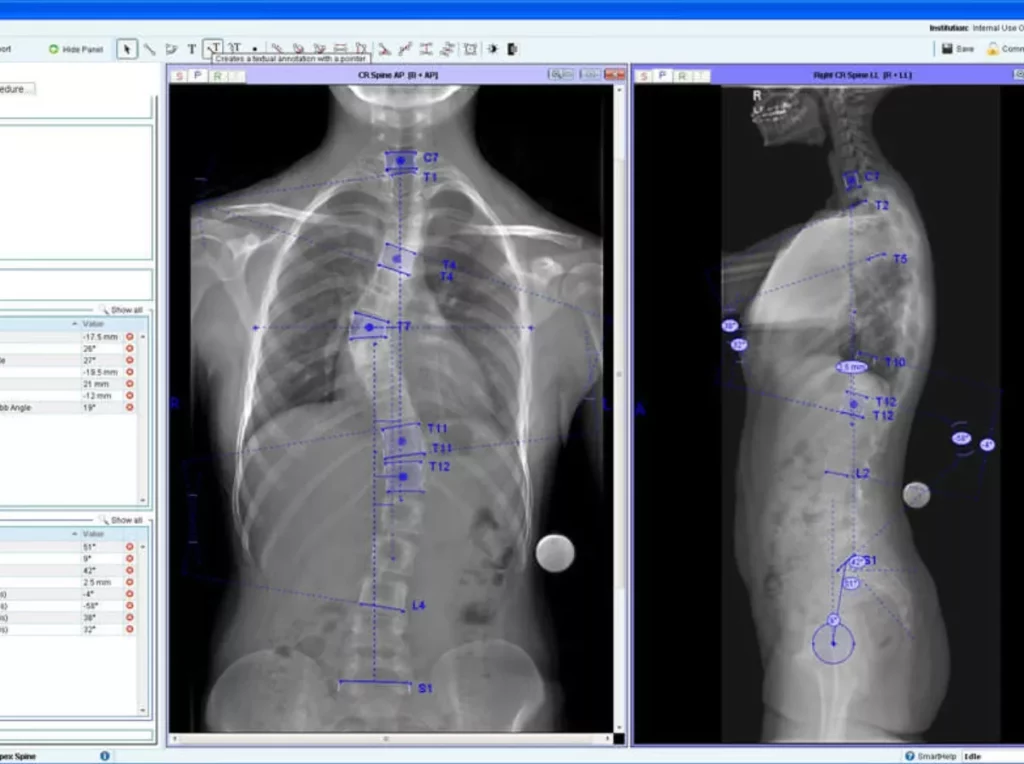

Santo Domingo.-La empresa local Ortotécnica firmó un acuerdo con la alemana HECTEC GmbH para la distribución exclusiva del software de planeación quirúrgica ortopédica MediCAD.

Con el mismo, los médicos ortopedas pueden planificar, simular y hacer cálculos biométricos de sus procedimientos quirúrgicos, con la posibilidad de integrar los implantes ortopédicos a su planeación gracias a la extensa base de datos de implantes, con más de 105 fabricantes de implantes internacionales ya integrados.

Las aplicaciones principales son cadera- remplazo articular, biometría, coxometría, FAI (Pincer, CAM), rodilla-reemplazo articular, osteotomías, hombro-reemplazo articular, mano-reemplazo articular, dedos-reemplazo articular y osteotomía-método Dror Paley.

En trauma, pie y tobillo- Hallux Valgus-reemplazo articular y columna vertebral-columna 3D. En 1994, HECTEC GmbH comenzó a desarrollar una solución que da a los cirujanos ortopédicos herramientas digitales para la planificación eficiente y segura de las cirugía articulares.